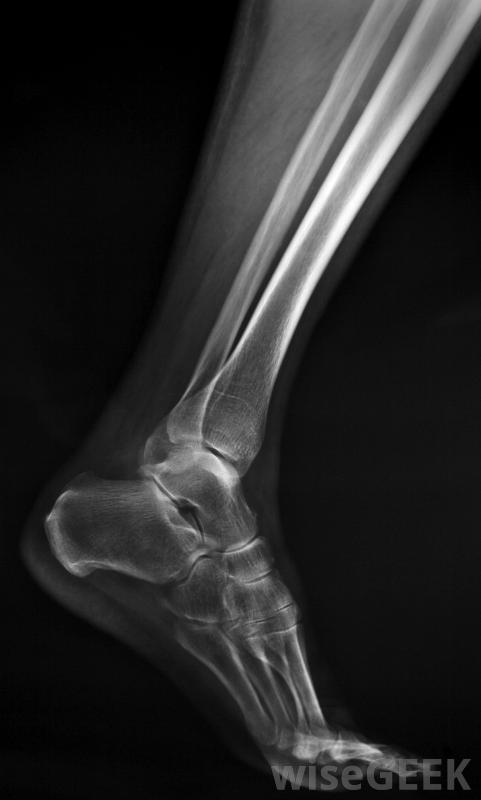

X光片可用于确定患者是否有脚踝骨折或扭伤踝关节疼痛是踝关节外伤的自然结果。当脚扭伤或扭伤时,可能会发生踝关节扭伤。从本质上讲,扭伤的脚踝是对控制踝关节运动的韧带的损伤。如果这些韧带被拉伸到扭伤和扭伤是导致踝关节疼痛的常见原因区分踝关节扭伤和踝关节骨折对于确定疼痛的原因很重要。踝关节长时间疼痛和肿胀通常表明骨折。当胫骨骨折时,踝关节骨折或者腓骨骨折踝关节骨折伴有瘀伤、肿胀和疼痛的症状,导致骨折仅被误认为是扭伤,踝关节骨折的修复需要手术和石膏关节炎是导致踝关节和足部疼痛的另一个常见原因。当踝关节磨损或受损时,会导致炎症或感染。通常情况下,运动员和体重过重的人会发展成关节炎,因为他们会使关节承受更大的压力。关节炎会导致脚失去稳定性,患者关节炎的症状包括踝关节和足部的疼痛和肿胀以及僵硬;治疗包括消炎药物减轻肿胀和注射可的松

脚或脚踝骨折可能需要石膏。

区分脚踝扭伤和脚踝骨折非常重要用于确定脚踝和足部疼痛的原因。